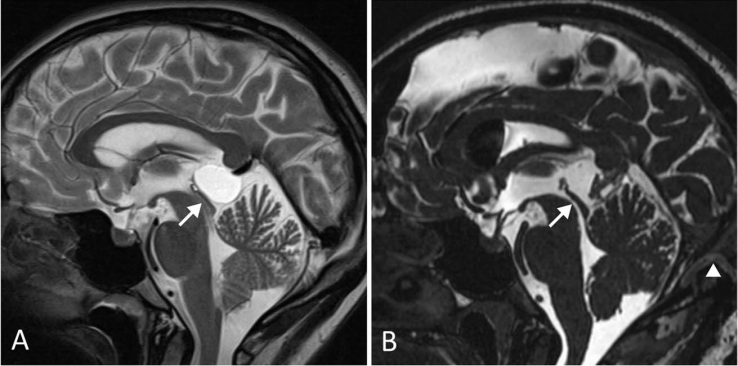

术前(A)可见松果体囊肿导致Sylvian大脑导水管狭窄(箭头),无脑积水表现。该患者表现为长期且逐渐加重的头痛。术后(B)囊肿完全切除,大脑中水管通畅,患者症状完全缓解。

较大的松果体囊肿可对顶盖板产生占位效应,导致上丘受压并引发帕里诺综合征;若压迫中脑导水管,则可引起梗阻性脑积水。症状有时可迅速进展,需要及时外科干预。松果体卒中是松果体囊肿最为凶险的急性并发症,指囊内出血后发生神经系统功能的急剧恶化。患者通常出现突发剧烈头痛,常伴有意识水平下降和脑膜刺激征。出血性松果体囊肿可发生于任何年龄,出血程度从囊内少量黄变液平到脑室内大量出血不等。有研究者指出,接受抗凝治疗的松果体囊肿患者发生囊内出血的风险可能增加,建议临床医生在告知此类患者抗凝或抗血小板治疗方案时,同时说明囊内出血的潜在风险。此外,文献中也有囊内出血以新发癫痫为首发表现的案例报道,需引起临床注意。